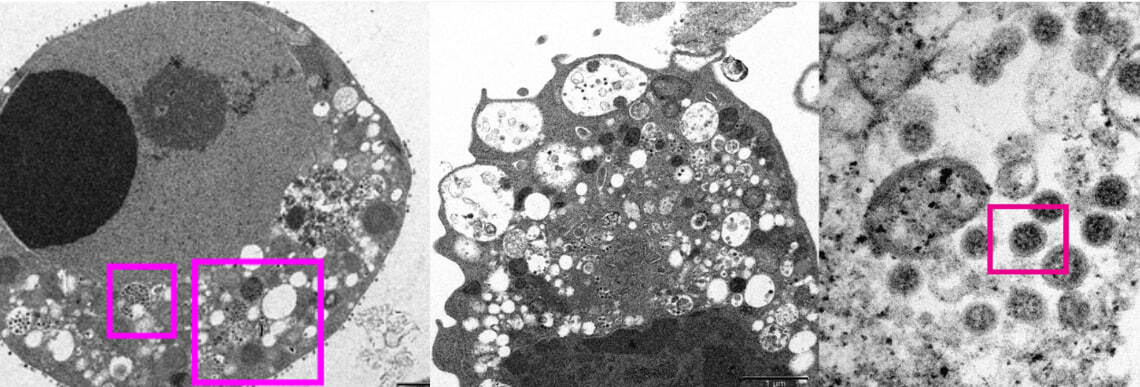

Медицинский факультет Университета Гонконга (HKUMed) опубликовал детальные изображения нового варианта коронавируса. Для получения снимков использовалась электронная микроскопия зараженных клеток почки обезьяны (Vero E6).

Видно повреждение клеток с опухшими пузырьками (везикулами), внутри которых содержатся маленькие черные вирусные частицы.

Заметны скопления вирусных частиц. На их поверхности отчетливо видны шипы в форме короны (именно их наличие определяет принадлежность к коронавирусам).